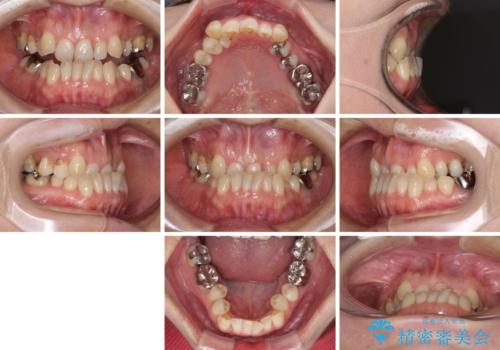

- 前歯の反対咬合を気にして来院された患者様です。

上顎骨の幅が下顎骨よりも小さいので、拡大装置により骨幅を広げて上下関係を改善すると同時にワイヤー矯正で反対咬合の改善を図り、その後インビザラインにて歯並びを整えることとしました。

上顎前歯の矮小歯は矯正治療の途中でオールセラミッククラウンを装着し、左右のバランスを整えることとしました。